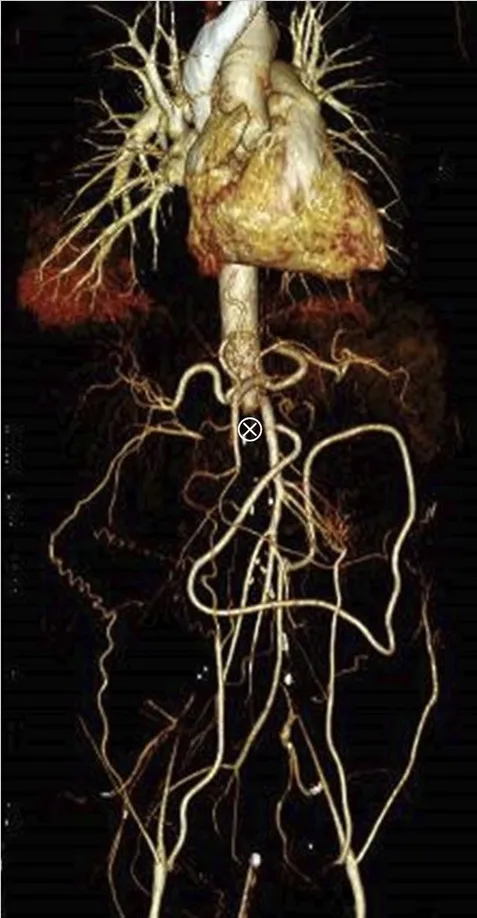

Se realizó una ecografía renal con Doppler que mostró ecogenicidad y tamaño renal normales, pero signos de oclusión aórtica en la emergencia de la arteria mesentérica superior, lo que fue confirmado por una tomografía computarizada con contraste (Figura 1).

La TC también reveló una importante circulación colateral en la pared abdominal, lo que permitía un suministro sanguíneo suficiente a las extremidades inferiores. Solo el riñón izquierdo mostró captación residual de contraste (Figura 1), lo que sugería un riñón derecho isquémico.

TC con contraste (reconstrucción 3D) mostrando oclusión aguda de la aorta justo superior a la arteria mesentérica. (A) Oclusión aórtica justo superior a la arteria mesentérica (marcada con un ⊗) junto con vasos colaterales en la pared abdominal (B) Riñón izquierdo con realce de contraste y riñón derecho sin realce, lo que sugiere falta de perfusión renal.